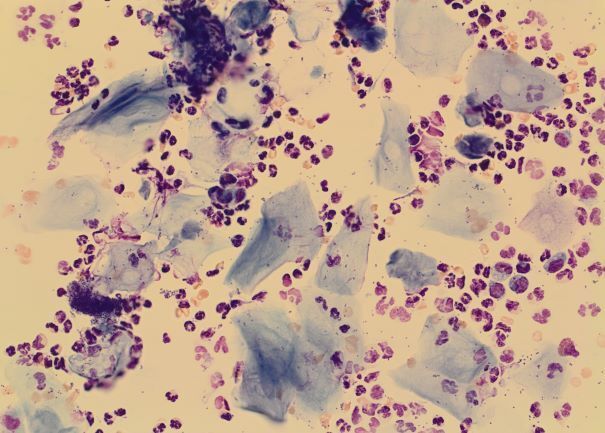

Feinnadelaspirate von Tumoren und Organen

Spülproben und Sekrete (z. B. BAL, TBS)

Punktate

Körperhöhlenergüsse